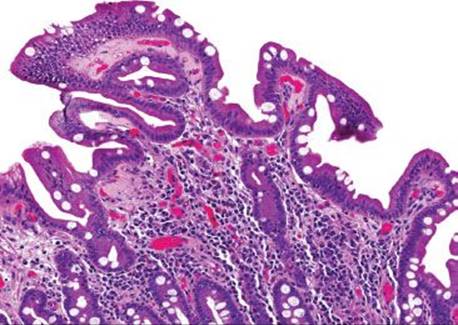

Figure 3.317 Isosporiasis. On higher power, a slight prominence of lamina propria eosinophils serves as a red flag to the diagnosis. Arrowheads highlight the Isospora organisms, which are obligate intracellular parasites and are found in the paranuclear or subnuclear cytoplasm.

Isosporiasis is among the more common protozoan causes of severe diarrhea in AIDS patients (Figs. 3.316–3.318).190 The Isospora belli organisms are spread via contaminated water or fecal–oral contamination. They localize to the small bowel surface and are exceedingly easy to miss owing to sometimes unremarkable background mucosa and sparsely distributed organisms (Figs. 3.316–3.321). Diagnostic confirmation is facilitated through identification of the oocysts in stool samples or duodenal aspirates.191 Standard therapy consists of trimethoprim–sulfamethoxazole, which is often long term in severely immunocompromised patients.